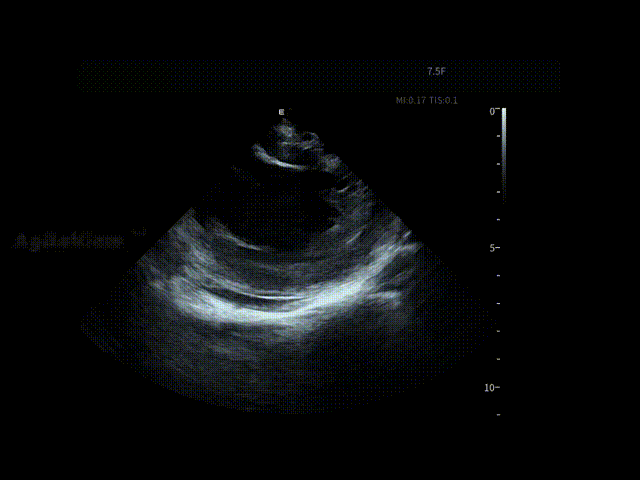

在全球最细7.5Fr ICE的持续影像引导下,手术路径清晰。随后,邹操教授在ICE下进行了房间隔穿刺,可见明显tenting现象。

随后,术者选择在AgileView™ ICE的“PFA预设模式”下进行导管消融,在实时高清影像的指导下,PulseSelect™脉冲消融导管安全进入左心房,先后完成双侧肺静脉隔离及后壁消融,ICE PFA预设模式下可见画面成像清晰,导管贴靠良好,整个消融过程顺利高效,消融时间仅30分钟(PVI+PWI)。术后患者恢复良好。

在消融过程中,ICE提供的实时高清成像帮助术者动态观察消融导管与心房组织的空间关系与贴靠状态,使关键步骤判断更加可视、可靠。

房间隔穿刺